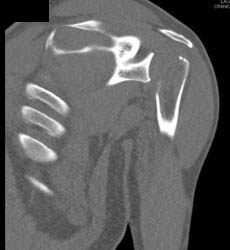

Diagnosis

Bakers Cyst